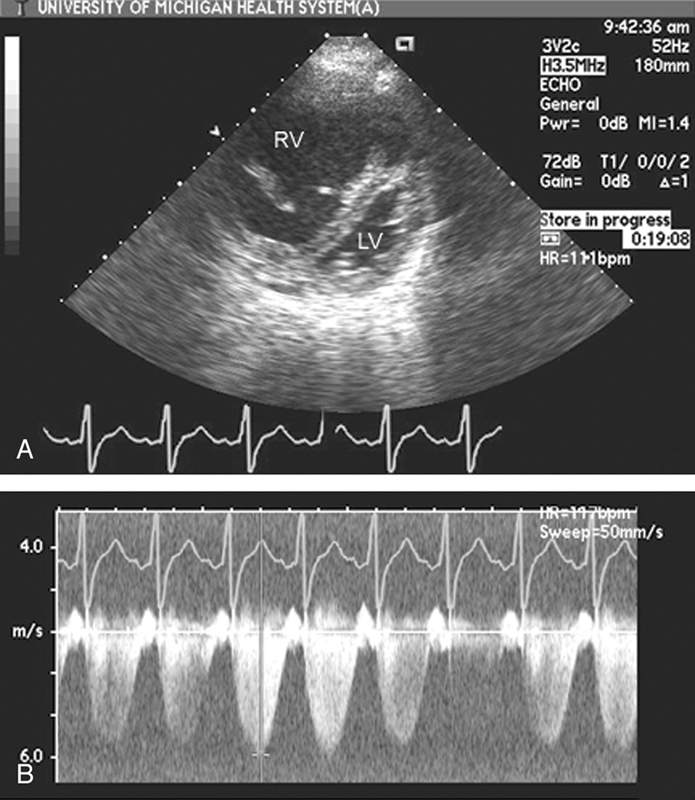

فحوصات تشخيصية لبعض امراض القلب والشرايين التاجية